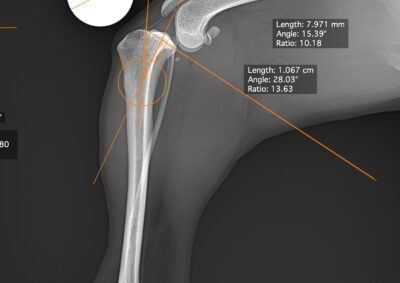

整形外科 注意 ボタンをクリックした先に、治療中および手術中の画像が説明で使用されている場合がございます。 そのような画像に弱い方は閲覧なさらないようお願いいたします。 整形外科 上腕骨外顆骨折の癒合不全 整形外科 大腿骨遠位開放および粉砕骨折 整形外科 膝蓋骨内方脱臼+前十字靭帯断裂 PGR#21+CBLO #251 整形外科 犬の前十字靭帯断裂に対するCBLO #250 整形外科 脛骨粉砕骨折 整形外科 内側鉤状突起分離症(Fragmented Medial Coronoid Process:F... 整形外科 股関節全置換術(トータル・ヒップ・リプレイスメント)#27 整形外科 橈骨固定術 #268 整形外科 橈骨固定術 #267 整形外科 橈骨固定術 #266 整形外科 股関節脱臼に対するBUSTOR #67 整形外科 脛骨粗面剥離骨折 <1234567> 症例カテゴリー 放射線治療整形外科軟部組織外科脳神経外科内科腫瘍外科救急・集中治療リハビリテーション科腫瘍内科内視鏡科脳神経科呼吸器外科中医・漢方猫の腎移植循環器科